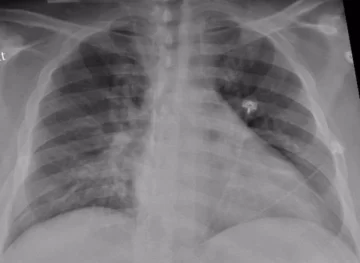

La neumonía es la principal causa de mortalidad por infección a nivel mundial y se ubica entre las 8 causas de muerte más comunes en adultos (2019), junto a la enfermedad pulmonar obstructiva crónica (EPOC) y el cáncer de pulmón. Además, según datos del estudio Global Burden of Disease, solo en 2019 fallecieron por neumonía más de 700.000 niños y un millón de personas mayores. ¿Qué debemos saber y cómo podemos prevenirla?

Los síntomas incluyen el aumento de producción de moco, fiebre, dolor torácico, dificultad respiratoria o falta de aire y dolor en puntada de costado. Si la persona presenta estos síntomas debe acudir a su médico para un diagnóstico certero y así poder acceder precozmente a un tratamiento adecuado.

El tratamiento para la neumonía implica la cura de la infección y la prevención de sus complicaciones. La mayoría de las personas que presentan neumonía adquirida en la comunidad (NAC) pueden recibir tratamiento en sus hogares. El médico decidirá el tratamiento específico, que dependerá del paciente (edad, antecedentes, etc.), y de la gravedad del cuadro clínico.

En Argentina la neumonía es la 6ª causa de muerte en general y la 5ª causa en mayores de 60 años. Además, la presencia de enfermedades cardiovasculares y de otras enfermedades aumenta el riesgo de sufrir formas graves. Se sabe que la vacunación, el diagnóstico precoz y el tratamiento también precoz con los antibióticos adecuados disminuyen el riesgo de morir por esta infección.